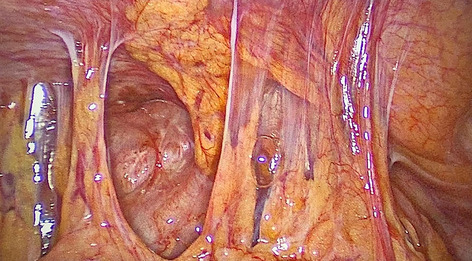

Introduction: Minimally invasive surgery and lately the usage of robotic technology has reduced the invasiveness of procedures, leading to improved patient outcomes after esophagectomy. The esophagogastric anastomosis represents a crucial step of the Ivor-Lewis procedure, as technical errors may lead to anastomotic leakage and severe postoperative morbidity. Anastomotic integrity is influenced by many different factors and there is great technical variety among surgeons. We have previously shown that a standardized 28-mm circular stapled anastomosis is very safe in Hybrid Minimally Invasive Esophagectomy. The aim of this study was to present and evaluate our standardized robotic circular stapled anastomotic technique in comparison to our large Hybrid patient collective.

Methods: Analysis of our prospectively collected, IRB approved database of hybrid, open, and robotic esophagectomies was performed. Starting 01/2019, we implemented an updated robotic standardized anastomotic technique using a circular stapler and ICG (indocyanine green) for our RAMIE cases at our academic center (Picture 1). Outcomes of patients undergoing this standardized robotic Ivor Lewis esophagectomy for esophageal cancer from 01/2019 – 11/2020 were compared to our overall cohort from 06/2016–06/2020 (Hybrid/Open group).Propensity score matching comparing robotic to hybrid procedures will be performed and data will be presented upon the meeting.